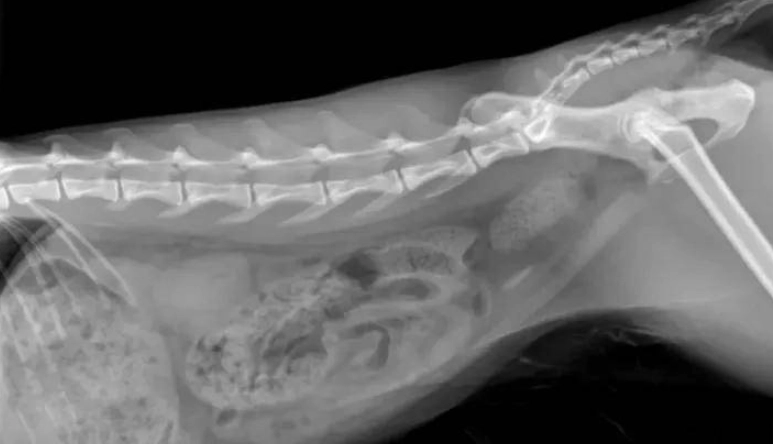

貓咪下泌尿道結石主要分兩大類,成分不同,處理方式天差地遠。獸醫通常需要透過尿液分析、X光、甚至超音波來判斷,光用猜的絕對不行。

| 草酸鈣結石 (Calcium Oxalate) | 草酸鈣 | 清晰可見(非常緻密) | 尿液偏酸性、遺傳、體質、飲食中鈣或草酸過高、或水分攝取不足導致尿液過濃。 |

1. 「從X光/超音波上看,結石大概是哪一種類型?有多大?有多少顆?」

這是所有判斷的基礎。要求看影像,親自看看那顆「石頭」長怎樣。